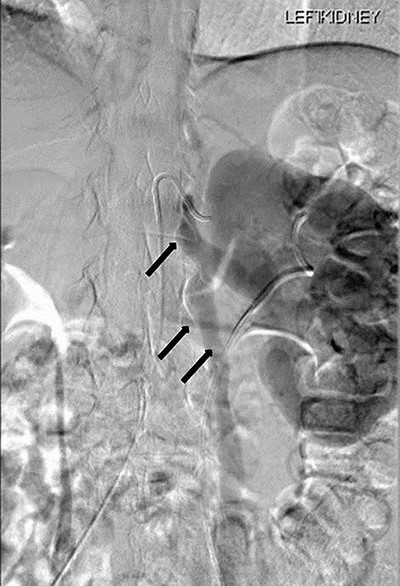

Renal angiography performed 1 day after the CT angiogram demonstrated no arteriovenous malformation. It showed a thin trickle of contrast passing through the LRV into the IVC (Fig. 6).

Renal angiography showing thin trickle of contrast passing through the LRV into the inferior vena cava (IVC) (top arrow), paraspinal collateral (middle arrow) and retrograde reflux of contrast into left ovarian vein (bottom arrow).